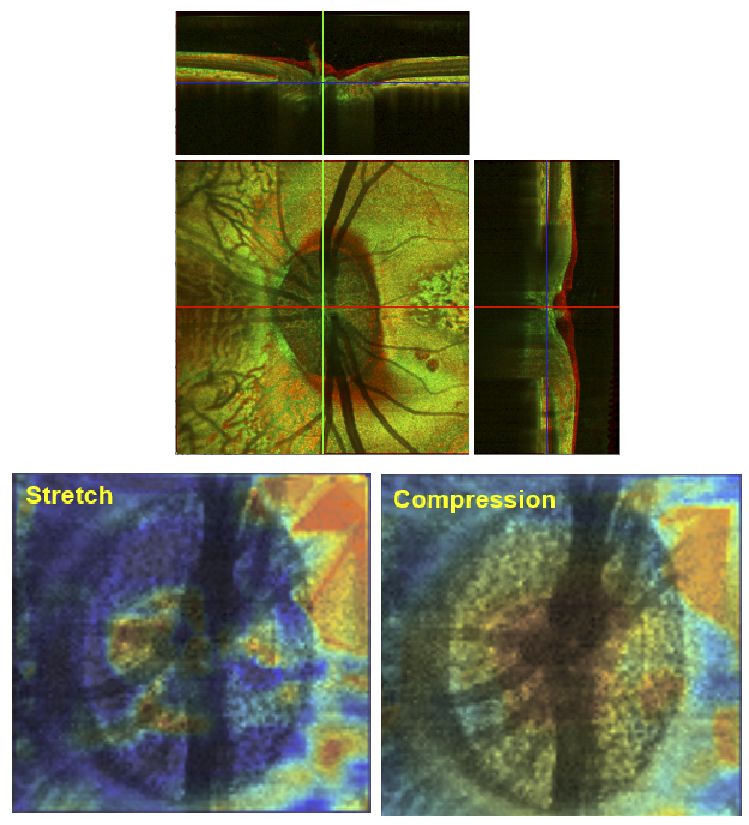

• Predicted Extension, Compression and Shearing of Optic Nerve Head Tissues

• IA Sigal, JG Flanagan, I Tertinegg and CR Ethier

• Experimental Eye Research, 85(3), 312-322, September 2007.

image